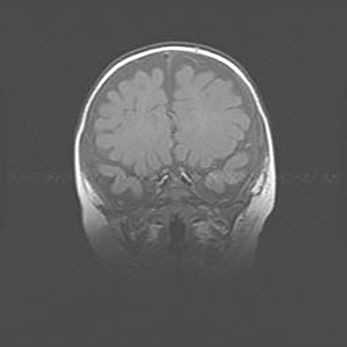

Открытая гидроцефалия.

Возраст: 9 месяцев 12 дней

Вес: 6800 г

Пол: мужской

Окружность головы: 41,5 см

Срок гестации: 28 недель

Гидроцефалия головного мозга у новорожденных имеет характерный признак: опережающий рост окружности головы приводит к визуально хорошо определяемой гидроцефальной форме сильно увеличенного в объёме черепа. Детские неврологи определяют следующие симптомы гидроцефалии у грудничков: выбухающий напряжённый родничок, частое запрокидывание головы, смещение глазных яблок к низу.